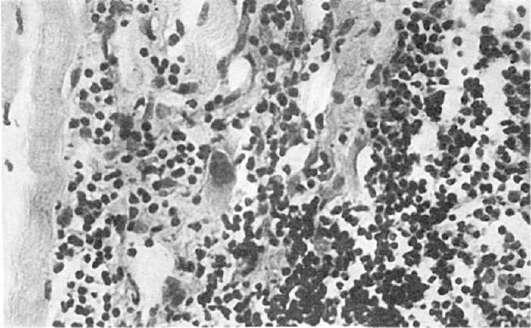

картину гломерулонефрита (см. Болезни почек). При волчаночном нефрите почки увеличены, пестрые, с участками кровоизлияний (рис. 179). При микроскопическом исследовании волчаночный нефрит характеризуется наличием патологических изменений в ядрах (гематоксилиновые тельца), утолщением капиллярных мембран клубочков,

принимающих вид проволочных петель, появлением гиалиновых тромбов иочагов фибриноидного некроза с фиксацией в них иммунных комплексов (рис. 180). В исходе волчаночного нефрита может возникать сморщивание почек с последующим развитием уремии.

Рис.

179. Почка при волчаночном нефрите